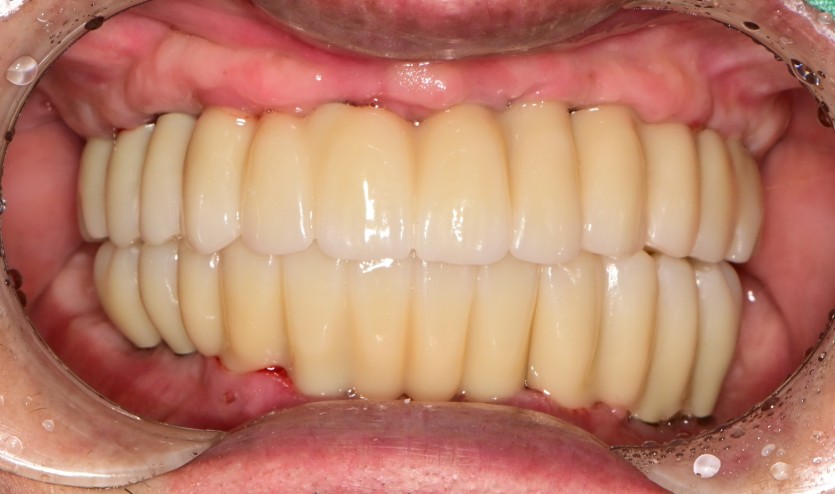

만 59세 전체 임플란트 증례

전체 임플란트 증례입니다.

18개의 임플란트로 완성하였습니다.